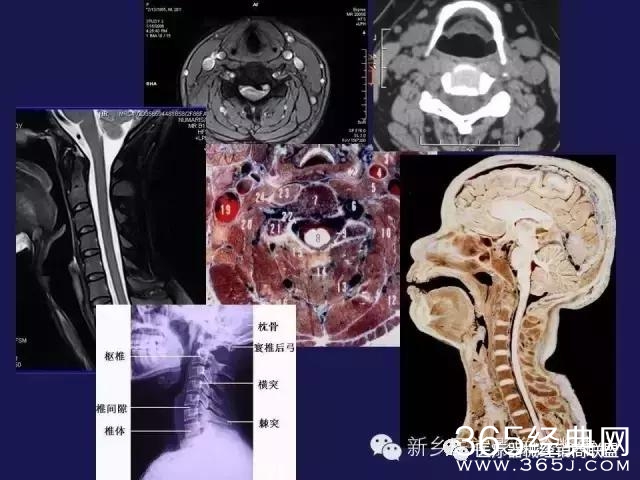

CT、MRI很难?NO,今日我们一起来学习一下如何读CT、MRI!

内行看门道:

整整90张图